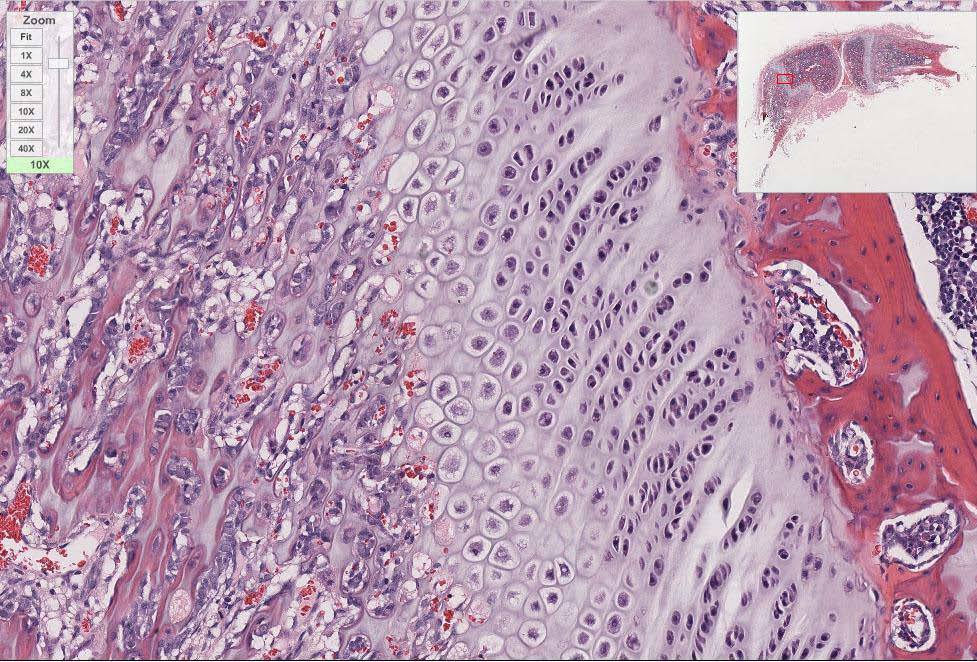

Identify the zone of proliferation in this growth plate of hyaline cartilage.

Identify the type of cartilage.

Fibrocartilage